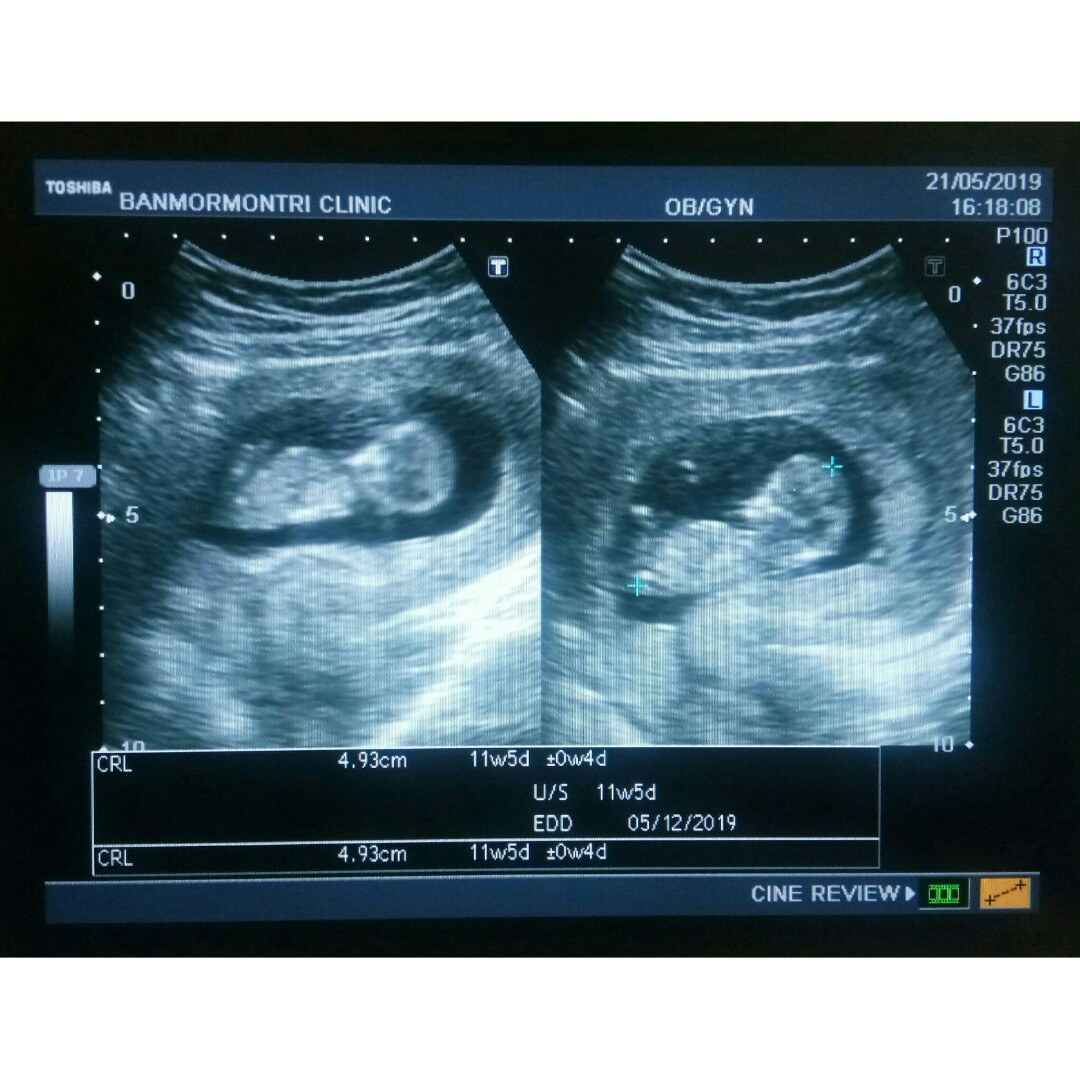

บ้านนี้ 11w จ้า